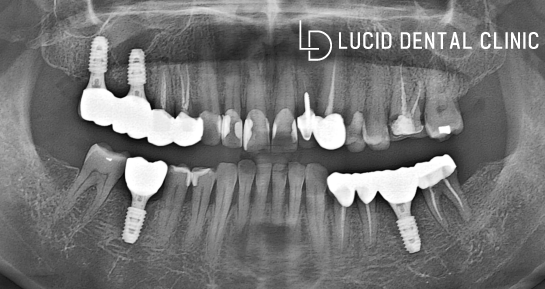

(2)

시간이 어느 정도 지나

나머지 부분도 치료를 마치고,

신논현역 치과 에 제작한

크라운 보철 체결을 진행했는데요

지르코니아 재료를 사용하여

만든 크라운을 체결했습니다.

마무리로 교합 높이를 점검하고,

표면을 매끄럽게 만들면 종료됩니다.

- 임플란트 수술 종료

충치로 인해 소실되고, 발치하여 빈

어금니로 불편했던 이전과 달리

튼튼한 픽스처를 통해 잃어버린

치아 기능을 되찾아드렸는데요

이전처럼 충치로 여러 질환이 나타나지 못하도록

계속해서 점검받고 관리하도록 당부해 드렸습니다.